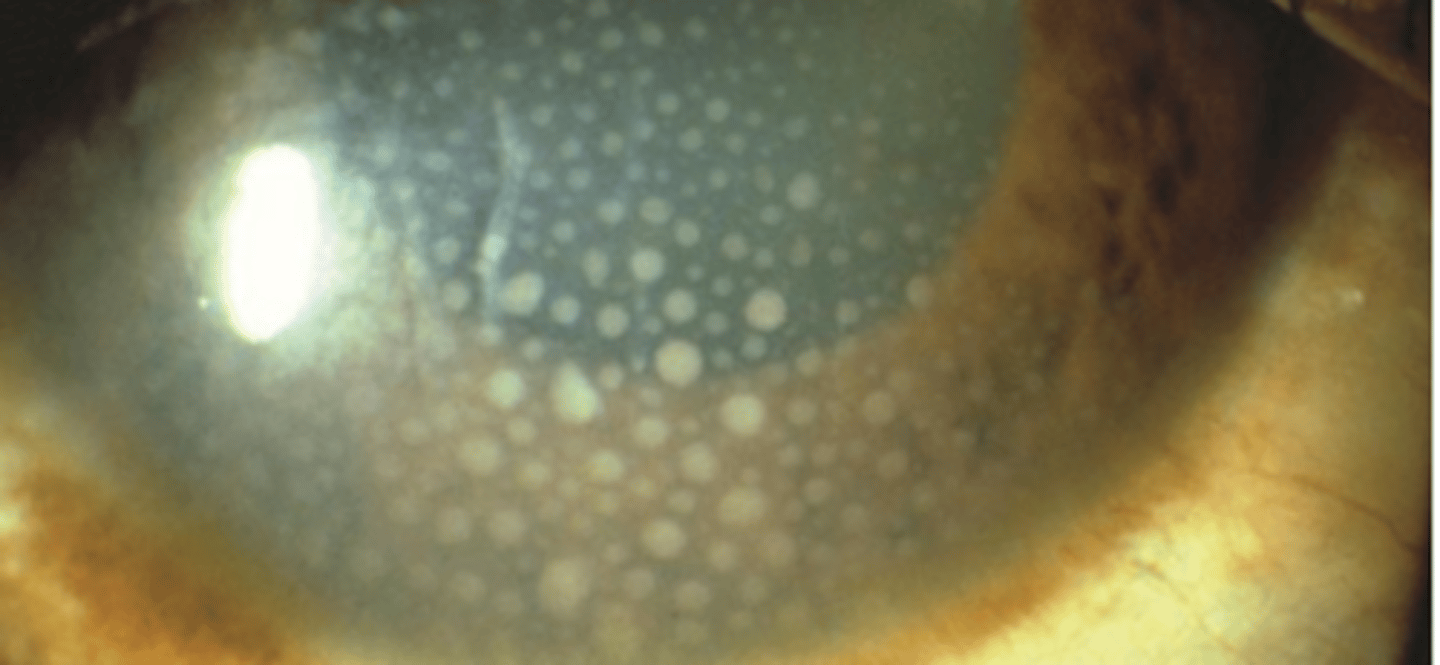

Keratic precipitates

inflammatory and white blood cells originating from the iris and ciliary body and adhering to the corneal endothelium.

Granulomatous

keratic precipitates that are larger and composed of macrophages. Have a greasy appearance and can be diffuse or localized.

Non-granulomatous

keratic precipitates that are smaller and composed of lymphocytes. Have a dust like appearance being white to slightly pigmented in color.